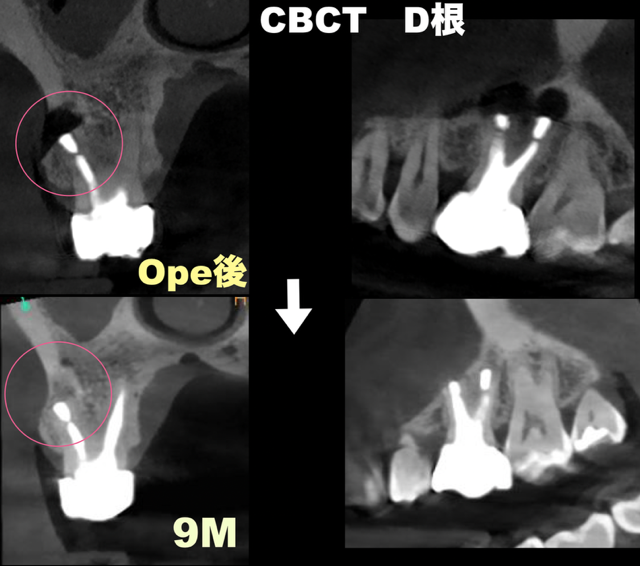

• 腫れを繰り返した奥歯(右上6番)。歯根端切除術で保存した症例。9ヶ月後の経過。

歯根端切除術の症例

2026.02.28

腫れを繰り返した奥歯(右上6番)。歯根端切除術で保存した症例。9ヶ月後の経過。